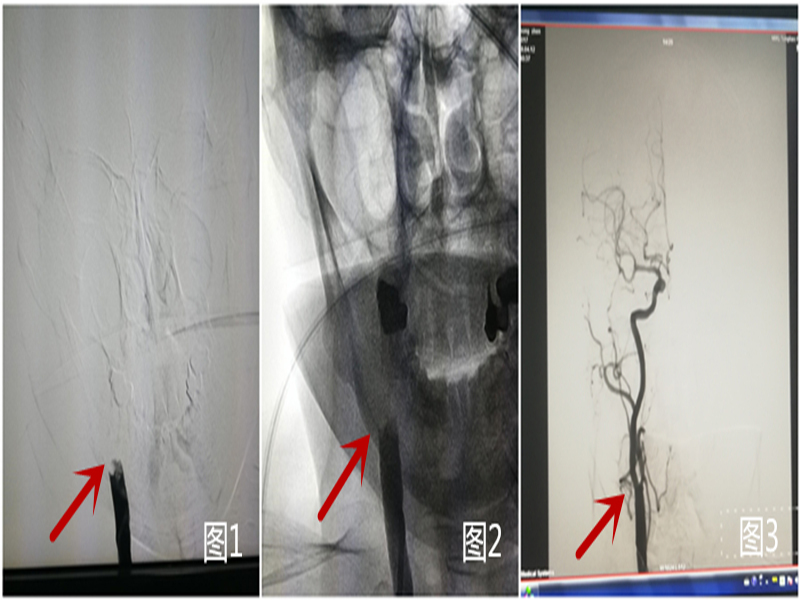

4.5 ( 1 2) ( 3)